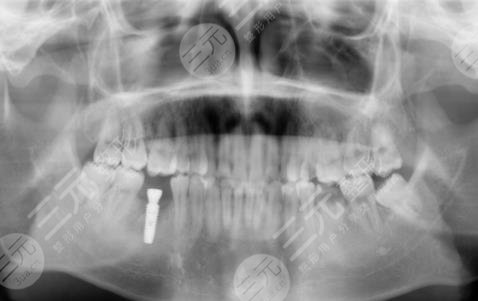

因为我真的十分喜欢吃糖,也就是很喜欢甜食,几乎每天都有很多的糖摄入,有的时候连吃米饭我想要吃甜的,这就导致了我的年纪轻轻牙齿就蛀了,因为糖吃多了,刚开始的时候还只是进行补牙,但是随着时间越来越久,我的牙齿的孔洞越来越大,然后没有办法就是拔掉了,我想着一直去补也不是问题,就跟父母商量之后,来到了镇江口腔医院进行种植牙。

医生看了我的牙齿情况之后,为我判断了几颗比较需要进行种植牙的地方进行了拔除。大概在拔完牙,一星期后我进行了种植牙,刚种上的时候还是觉得挺不舒服的,但是随着时间的推移,我逐渐适应了自己的种植牙,并且种植的牙齿比之前更加洁白,它不单单解决了我的口腔问题,还让我整个人的气质都上升了不少呢。